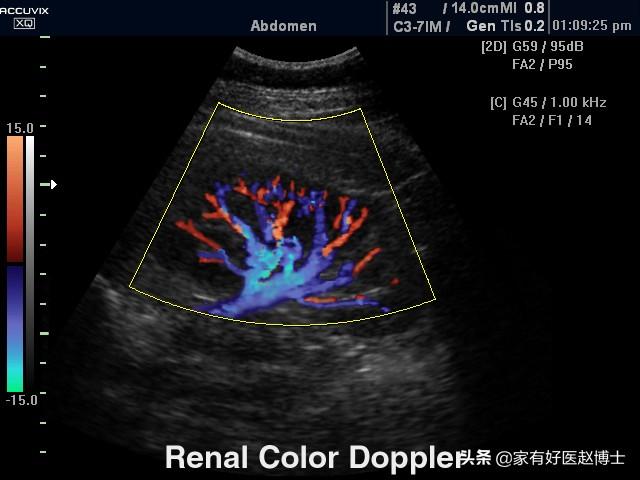

腎臓超音波検査

腎動脈の超音波検査はカラードップラー超音波フローイメージングとも呼ばれ、腎動脈の血流に対する抵抗の指標を評価する。高血圧による腎障害は、腎の葉間動脈の血流に対する抵抗の増加を最初に引き起こすことが示されており、そのため腎動脈超音波検査で評価される腎葉間動脈の血流抵抗指数は、高血圧性腎障害の早期診断にも有用である。